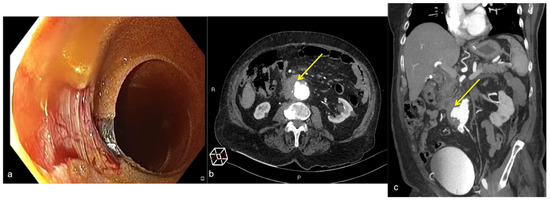

| Dieulafoy Lesion (Figure 27) | Melaena, haematemesis, haematochezia, or a combination of more than one of these signs, depending on the location of the lesion. | Abnormally enlarged submucosal vessel, which may appear tortuous, linear or as a non-specific “blush” of contrast medium at the mucosal/submucosal level. |

| Aorto-Gastric Fistula (Figure 28) | Copious bleeding. | A connection between the aorta and the gastric lumen. Absence of adipose cleavage planes. |

- Martino, A.; Bennato, R.; Oliva, G.; Pontarelli, A.; Picascia, D.; Romano, L.; Lombardi, G. Primary aortogastric fistula: An extraordinary rare endoscopic finding in the setting of upper gastrointestinal bleeding. Endoscopy 2021, 53, E60–E61. [Google Scholar] [CrossRef]